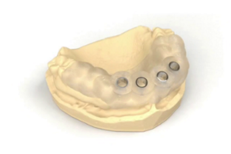

SIMPLANT : un guide chirurgical inégalé!

BellaTek Encode Biomet 3i

Une seule prise d'empreinte sur le pilier de guérison !

Le système de prise d’empreinte BellaTek Encode® offre aux praticiens des solutions optimisées en éliminant l’utilisation de transferts d’empreinte sur l’implant. Le protocole de traitement est ainsi simplifié pour le chirurgien, le prosthodontiste et le laboratoire. De plus, les patients sont satisfaits et les résultats esthétiques sont au rendez-vous.